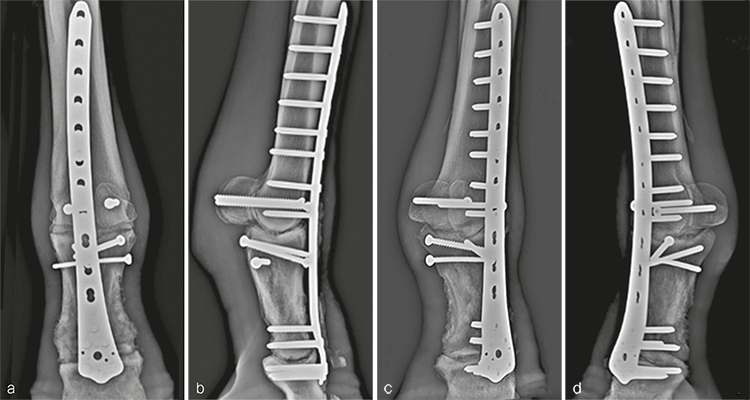

The cast was changed 2 weeks postoperatively and removed 1 month following the repair. The distal limb was maintained in a Robert-Jones bandage for 1 additional month. Routine hoof care in conjunction with rocker shoes and silicone padding were initiated at the time of cast removal. The mare made excellent progress postoperatively and was fully weight bearing on the repaired leg immediately. Radiographic evaluation 5 months postoperatively confirmed good fracture healing and progression of the arthrodesis (Fig 6). The mare was returned to paddock activity at this time and was fully functional with only mild mechanical lameness, as expected with arthrodesis of the metacarpophalangeal joint.

Postanesthetic myopathy complicated the patients recovery and necessitated intensive care immediately following surgery. He responded to supportive therapy and improved rapidly. In addition, his comfort level was excellent on his operated leg for the duration of hospitalization. At 3 months postoperatively, clinical evaluation revealed excellent weight bearing on the operated leg (Fig 8a), with mechanical lameness characteristic of horses with a fused metacarpophalangeal joint. The cosmetic appearance of the distal limb was excellent (Fig 8bc). Radiographic examination demonstrated excellent fracture healing with ongoing progress of the arthrodesis in both articulations (Fig 9). He was shoed with rocking shoes and silicone padding on both front feet to facilitate mobility and to provide hoof support.